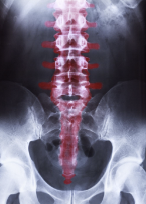

허리 척추협착증의 치료 방법은 증상의 심각성과 개인의 상황에 따라 다양하게 적용됩니다. 아래는 일반적으로 적용되는 치료 방법입니다.

허리 척추협착증의 초기 증상에서는 보존적 치료로 치료할 수 있습니다. 이는 통증을 완화하고 척추 채널을 넓히기 위한 물리 치료, 체중 감량, 운동 치료 등을 포함합니다. 물리 치료는 열 또는 냉, 전기 및 초음파를 사용하여 근육 이완 및 통증 완화를 돕습니다. 체중 감량은 척추에 가해지는 압력을 감소시키고 척추 채널의 크기를 늘리는 데 도움이 됩니다. 운동 치료는 척추 채널을 넓히는 데 도움이 됩니다.

보존적 치료가 효과적이지 않은 경우, 진통제 및 항염제와 같은 약물 치료가 필요할 수 있습니다. 진통제는 통증을 완화하고, 항염제는 염증을 완화하며 척추 채널을 압박하는 부위의 염증을 감소시키는 데 도움이 됩니다.

척추 교정술 허리 척추협착증이 심한 경우, 척추 교정술을 고려해 볼 수 있습니다. 척추 교정술은 척추 채널을 넓히고 압박을 감소시키는 수술입니다. 이 수술은 종종 열공법(전통적인 수술)과 경피적 척추 내시경 수술(교정술 중 최신기술)로 진행됩니다.

인공 디스크 치환술

인공 디스크 치환술은 디스크의 변성이나 손상으로 인해 발생하는 척추 채널의 좁아짐을 개선하기 위한 수술입니다. 이 수술은 디스크를 제거하고 인공 디스크로 교체하는 것입니다.

허리 척추협착증은 치료하기 어려운 질환 중 하나입니다.